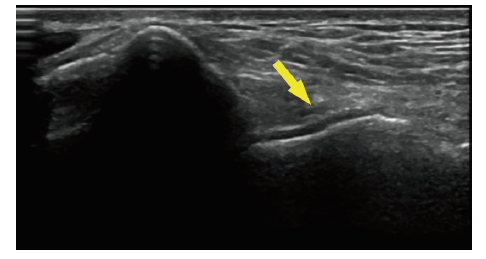

图2 一例22岁男性急性GA患者发作关节的MSUS检查结果

注:该例患者因“右踝关节肿痛2 d”就诊,其MSUS在右踝关节外踝区可见典型双轨征表现(箭头处)。